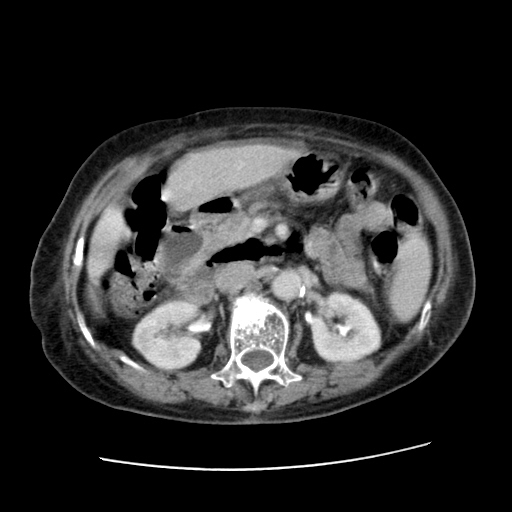

标题: CT25203:上腹部增强,看看

女,77.无不适

肝脏变异、异位胆囊,肝右叶肝内胆管结石并肝内胆管扩张。

肝右叶肝内胆管结石并肝内胆管扩张。

肝右叶肝内胆管结石并肝内胆管扩张

胆总管扩张

肝右叶肝内胆管结石并肝内胆管扩张。胆总管下段梗阻,考虑壶腹部占位。

右侧肝内胆管局限性扩张,其内密度不均匀,扩张的胆管壁增厚,考虑肝内胆管炎合并结石可能性大

肝右叶肝内胆管结石并肝内胆管扩张。胆总管下段梗阻,考虑壶腹部占位。支持